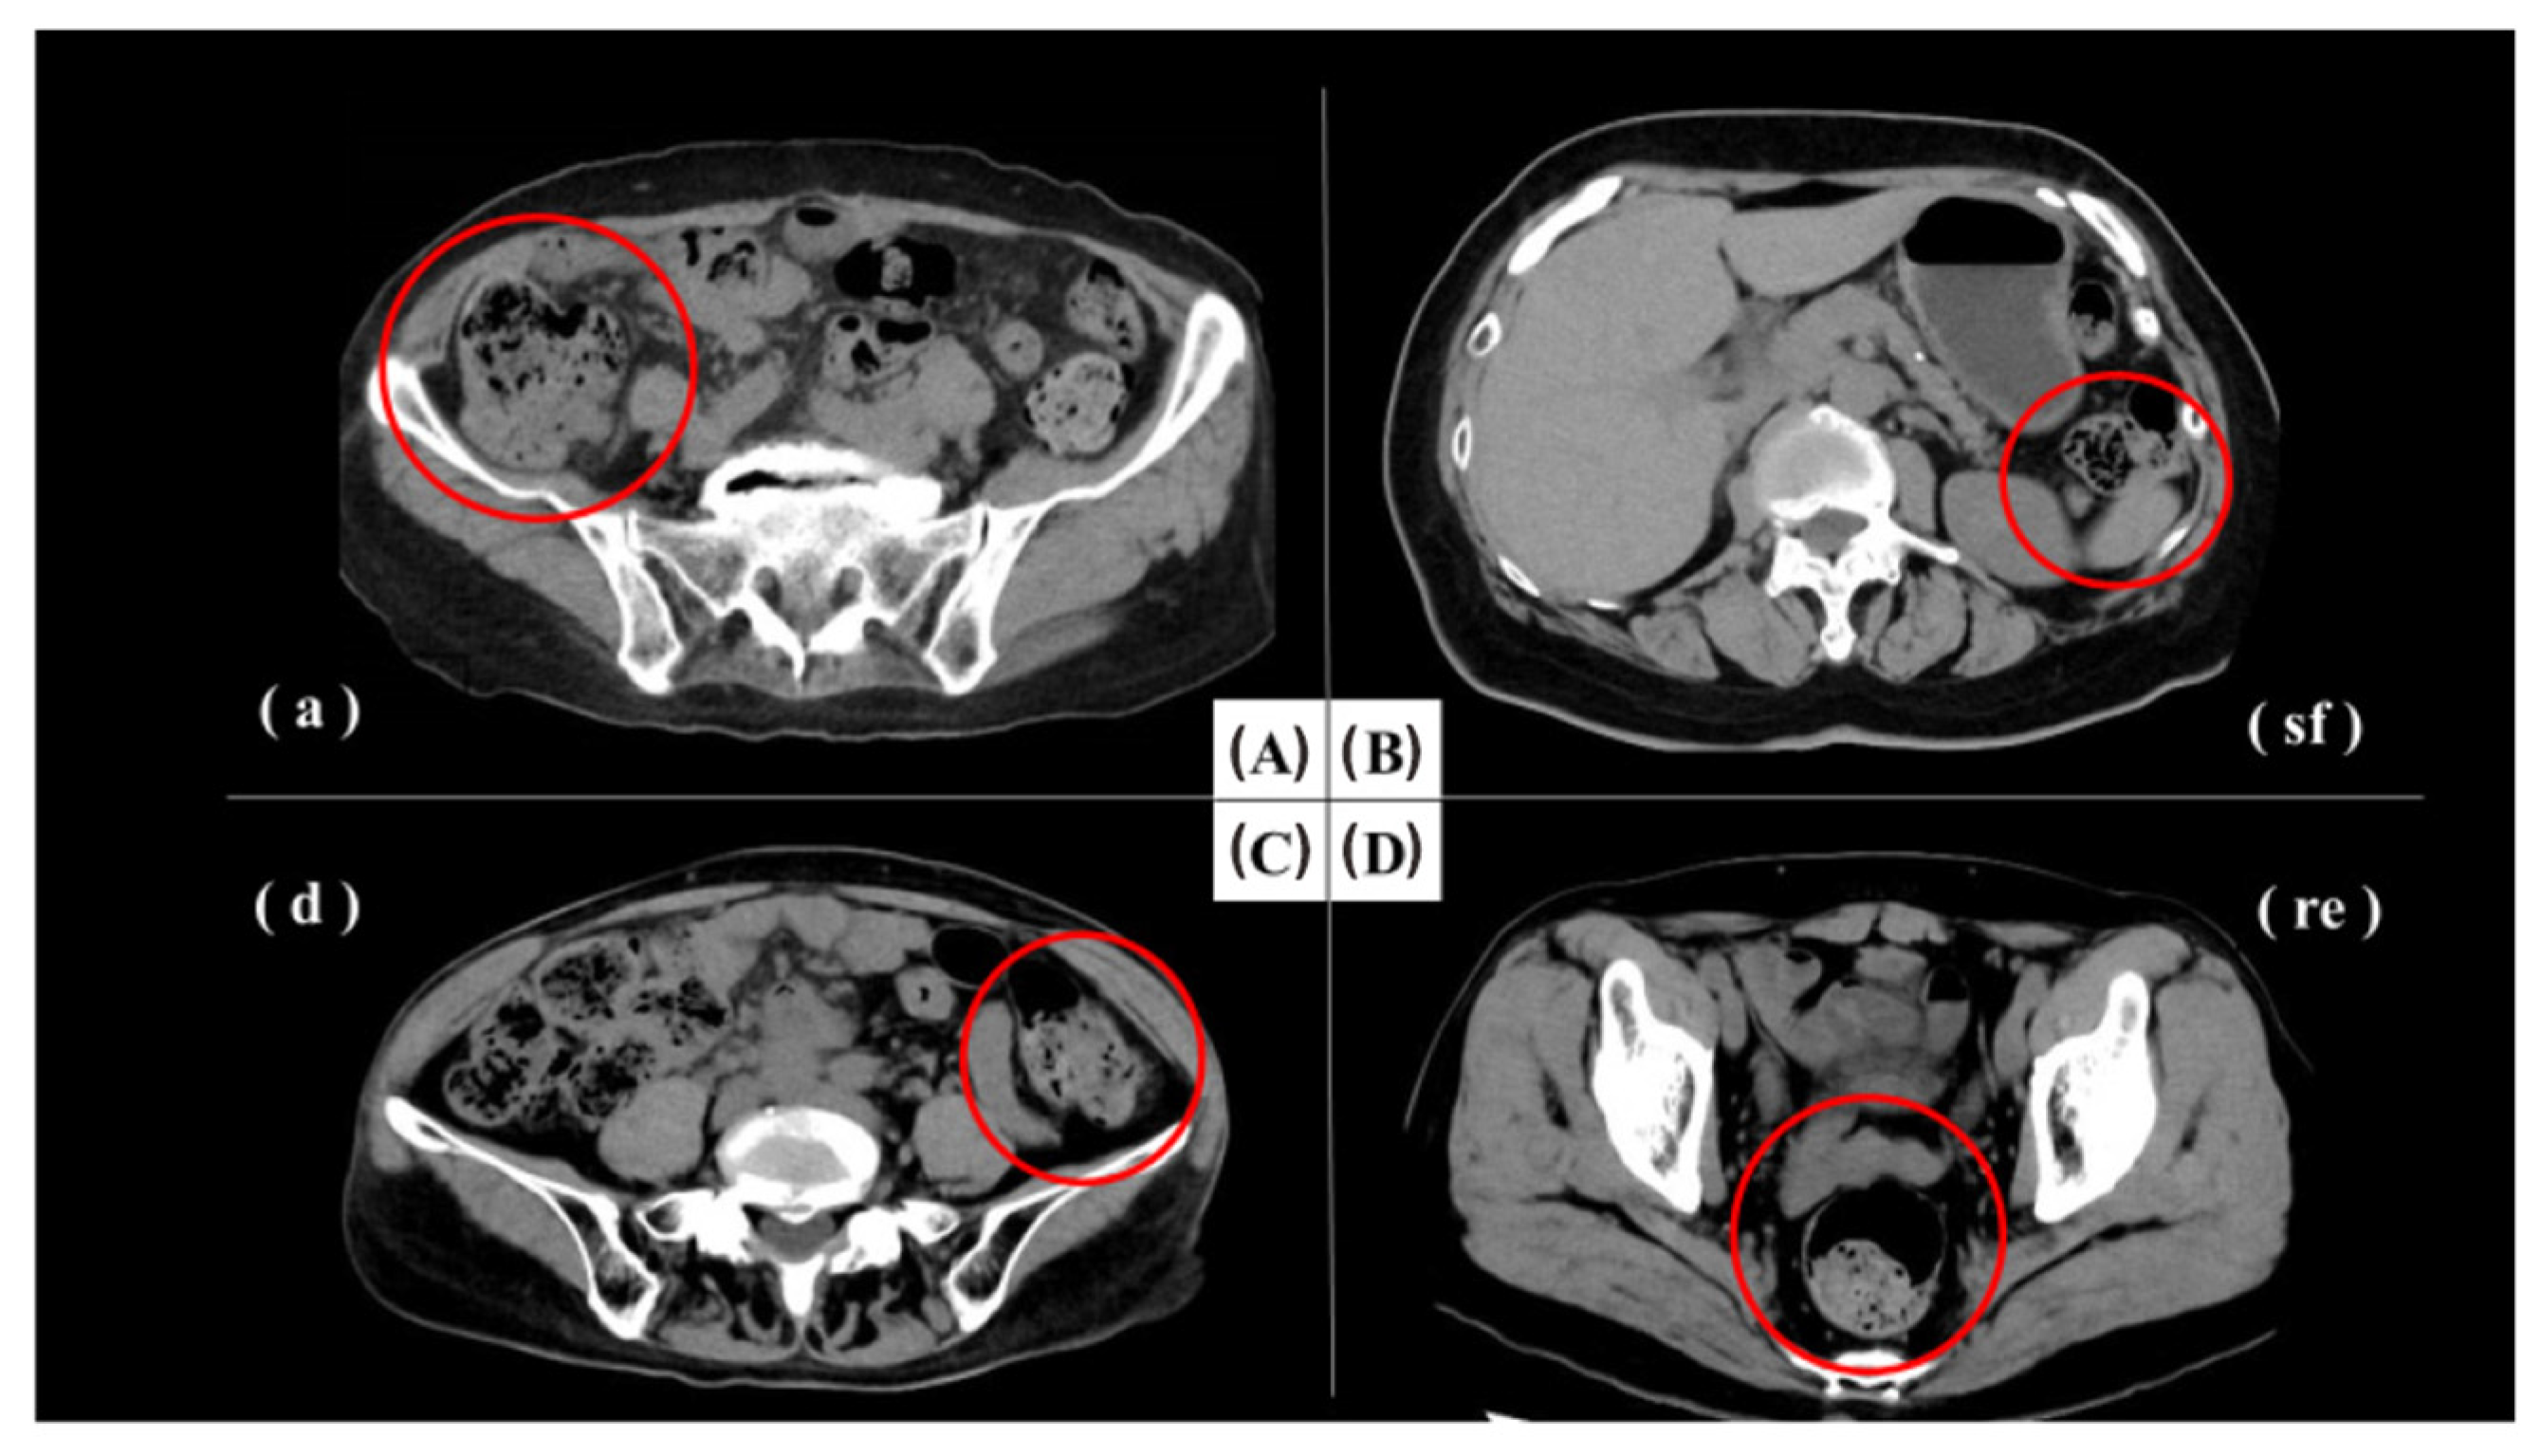

- Bennett, G.L.; Birnbaum, B.A.; Balthazar, E.J. CT of Meckel’s diverticulitis in 11 patients. Am. J. Roentgenol. 2004, 182, 625–629. [Google Scholar] [CrossRef] [PubMed]

- Kumar, M.; Singh, P.; Kumari, P.; Kaushik, R. Revisiting the forgotten remnant: Imaging spectrum of Meckel’s diverticulum. SA J. Radiol. 2022, 26, 2431. [Google Scholar] [CrossRef]

- Thurley, P.D.; Halliday, K.E.; Somers, J.M.; Al-Daraji, W.I.; Ilyas, M.; Broderick, N.J. Radiological features of Meckel’s diverticulum and its complications. Clin. Radiol. 2009, 64, 109–118. [Google Scholar] [CrossRef]

- Elsayes, K.M.; Menias, C.O.; Harvin, H.J.; Francis, I.R. Imaging manifestations of Meckel’s diverticulum. Am. J. Roentgenol. 2007, 189, 81–88. [Google Scholar] [CrossRef] [PubMed]